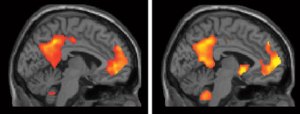

Instead, we need to recognise our own power of imagination. We use the same parts of our brain in imagining as we do in remembering. Your ‘brain’ doesn’t really know that your big vision hasn’t already happened; therefore you are the only blocker to your dreams. Your limiting self-beliefs, your why-nots. So let’s take advantage of our sophistication. Let’s blow the doors off everything that limits us. Let’s all start to have visions that we’re proud of: our reality is what we make it.